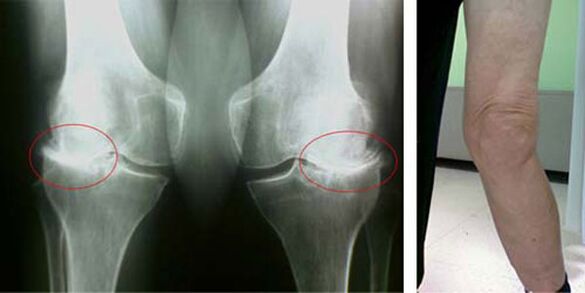

In a healthy knee joint, cartilage is a type of layer that does not allow bones to touch, therefore, eliminating the possibility of damage when walking. Diseased cartilage is unable to cope with this function, therefore, signs of stiffness appear in the joints during movement, accompanied by pain. This condition becomes permanent as a result of internal pathological changes, when the thinning of cartilage tissue leads to thickening of the bones and creates conditions for the appearance of bone spurs - osteophytes, which cause acute pain.

The early stages of pathology such as arthrosis of the knee joint do not visually manifest themselves in any way. However, after a certain time, the patient notices signs of knee deformity, as well as characteristic curvature along the axis of the lower leg (directed inwards). There is also dryness when you have to bend the legs.

The presence of pain, limited movement in the knee makes a person see a doctor and undergo an examination. To do this, he needs to pass a test and take an x-ray of the diseased joint. If these measures are not sufficient to confirm arthrosis of the knee joint, then magnetic resonance imaging is performed. Based on the data collected, the doctor chooses the best method of treatment.